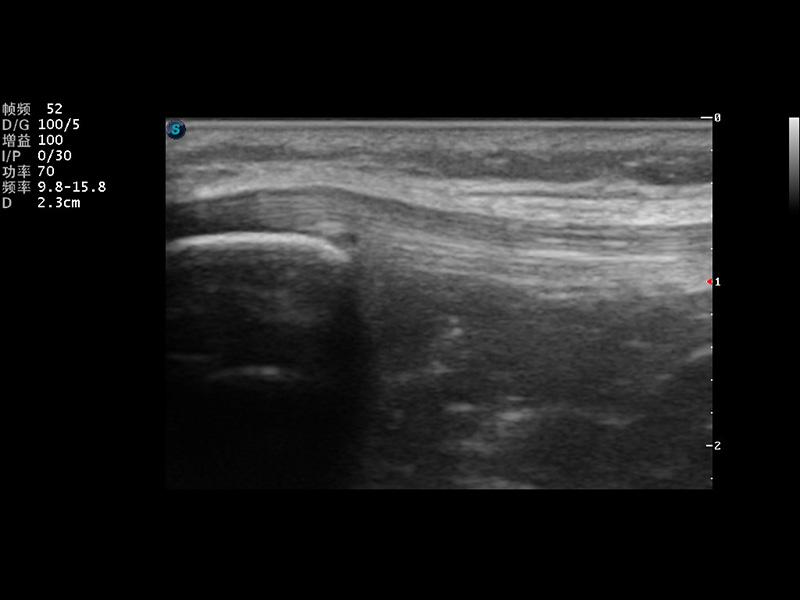

S9便携式彩色多普勒超声诊断仪是球速体育入口研发的高端便携彩超设备,外观设计新颖、产品性能卓越。S9在便携超声领域采用了突破传统的触摸屏交互设计,并以先进的软件硬件技术和设计理念,为您带来清晰的图像质量、稳定的工作性能和便捷的操作体验。

μ-Scan微米成像